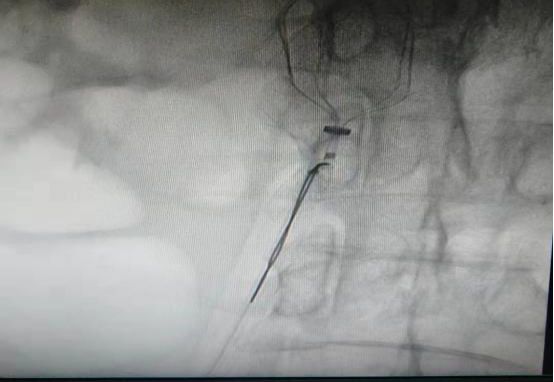

(6)2018年12月13日开展第一例颅内动脉瘤栓塞术。

患者:赵某  女性 48岁 河南省光山县

图片